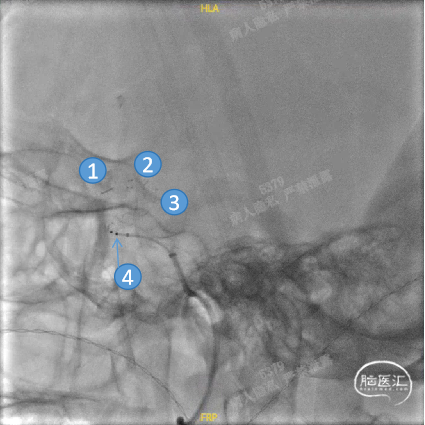

Headway™ 27 156cm微导管内输送FRED 4012血流导向密网支架,系统远端精准定位于预计着陆区远端,回撤微导管原位释放支架,头端即刻打开且锚定牢固后,继续原位释放支架。

正位

①输送导丝头端

②支架远端扩口显影点

③工作区螺旋显影丝

④支架近端扩口显影点

平衡释放支架中段,过弯时确保系统头端处于血管中央,观察到支架自膨打开后,轻推支架以保证支架贴壁。确定近端着陆点处于血管平直区且贴壁良好后,平衡释放支架末端并解脱。